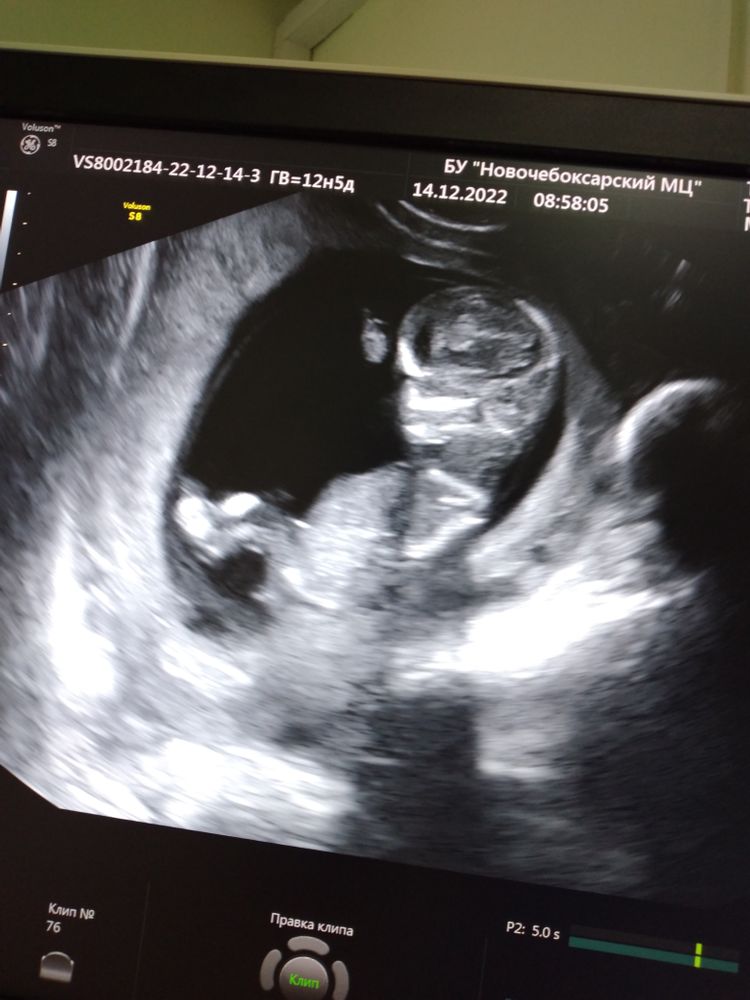

1 скрининг🥰наконец то

В общем пишу, у нас вчера было 12,5 неделек, был 1 скрининг, пошла я в нашу ЖК, конечно предполагала как все пройдёт.. Толком ничего не сказали, только что все хорошо, не показали, сердце включили доя себя, а я толком и не послушала...подумываю сходить просто для себя в платную клинику.Ну а так, пишут все хорошо, но так быстро посмотрели...минут 7, а все пишут минут 30 смотрят...

Я спросила можно ли предположить пол, врач такая (ну мальчик или девочка)🤦♀️я говорю понятное дело, в общем все ясно с ними..ладно хоть дали с телефона экран сфоткать.. фото они не делают платно, думаю ну ладно.Уже такие большие стали😍приятно все таки видеть свою кроху❤